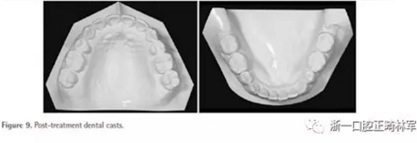

治療后面部和口內(nèi)照片顯示治療結(jié)果很成功(Figure 8)?;颊叩拿嫘瞳@得了非常顯著的改善,尤其是在唇部區(qū)域。覆合從-3.5mm增大到3.5mm,覆蓋從1.2mm增大到2.0mm。獲得了I類磨牙關(guān)系,沒有擁擠(Figures8 and 9)。

全景片顯示上前牙區(qū)未發(fā)生進行性牙根吸收。然而,在下磨牙區(qū)有輕度牙根吸收,并且牙根平行性有改善空間(Figure 10A)。